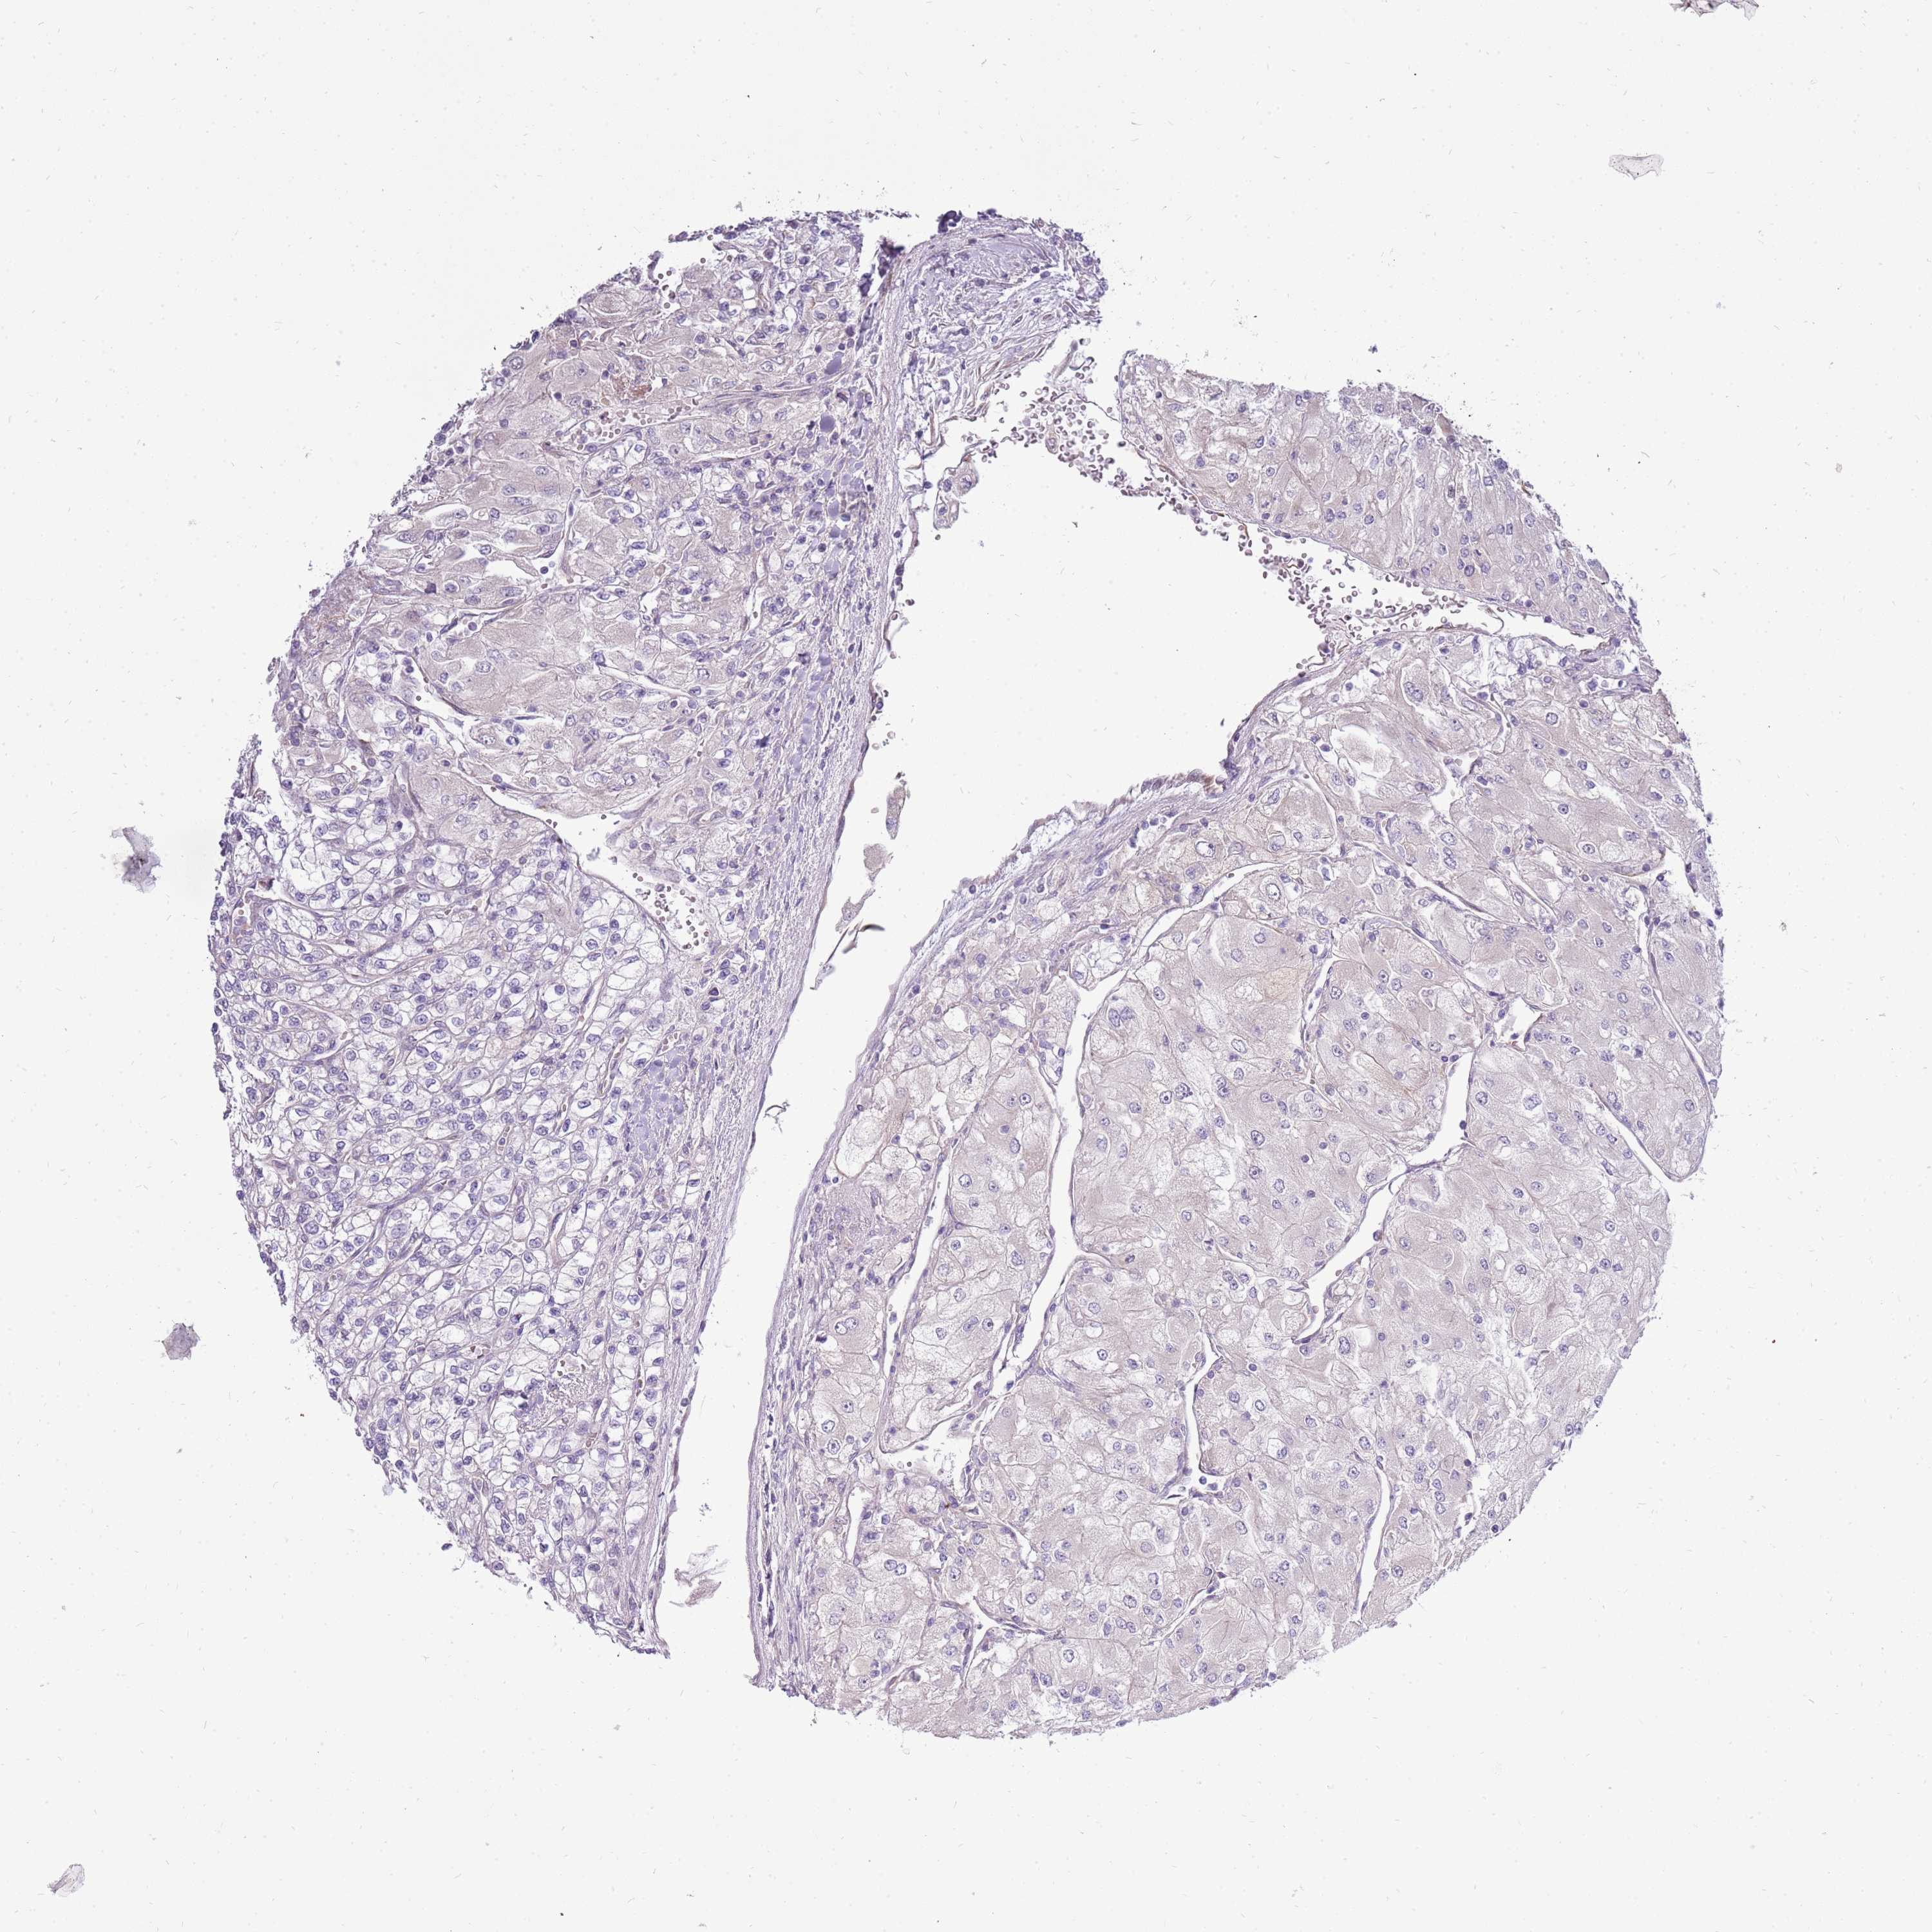

KIDNEY RENAL PAPILLARY CELL CARCINOMA (TCGA) - Interactive survival scatter ploti

The Survival Scatter plot shows the clinical status (i.e. dead or alive) for all individuals in the patient cohort, based on the same data that underlies the corresponding Kaplan-Meier plots. Patients that are alive at last time for follow-up are shown in blue and patients who have died during the study are shown in red.

The x-axis shows the expression levels (FPKM) of the investigated gene in the tumor tissue at the time of diagnosis. The y-axis shows the follow-up time after diagnosis (years). Both axes are complimented with kernel density curves demonstrating the data density over the axes. The top density plot shows the expression levels (FPKM) distribution among dead (red) and alive patients (blue). The right density plot shows the data density of the survived years of dead patients with high and low expression levels respectively, stratified using the cutoff indicated by the vertical dashed line through the Survival Scatter plot. This cutoff is automatically defined based on the FPKM cutoff that minimizes the p-score. The cutoff can be changed by dragging the vertical line or by entering a cutoff value in the square labeled "Current cut-off".

Under the Survival Scatter plot the p-score landscape (black curve; left axis) is shown together with dead median separation (red curve; right axis). Dead median separation is the difference in median mRNA expression between patients who have died with high and low expression, respectively. It is calculated as follows: median FPKM expression of dead patients with high expression - median FPKM expression of dead patients with low expression. This is intended to aid the user in visually exploring custom cutoffs and the associated p-scores and dead median separation.

Individual patient data is displayed and can be filtered by clicking on one or more of the category buttons on the top of the page. Categories describing expression level and patient information include: high, low, alive, dead, female, male and tumor stages. The scale of the x-axis can be toggled between linear and log-scale by clicking on the "x log" button. Mouse-over function shows TCGA ID, patient information and mRNA expression (FPKM) for each patient.

& Survival analysisi

Kaplan-Meier plots summarize results from analysis of correlation between mRNA expression level and patient survival. Patients were divided based on level of expression into one of the two groups "low" (under cut off) or "high" (over cut off). X-axis shows time for survival (years) and y-axis shows the probability of survival, where 1.0 corresponds to 100 percent.

UGGT2 is not prognostic in Kidney Renal Papillary Cell Carcinoma (TCGA)